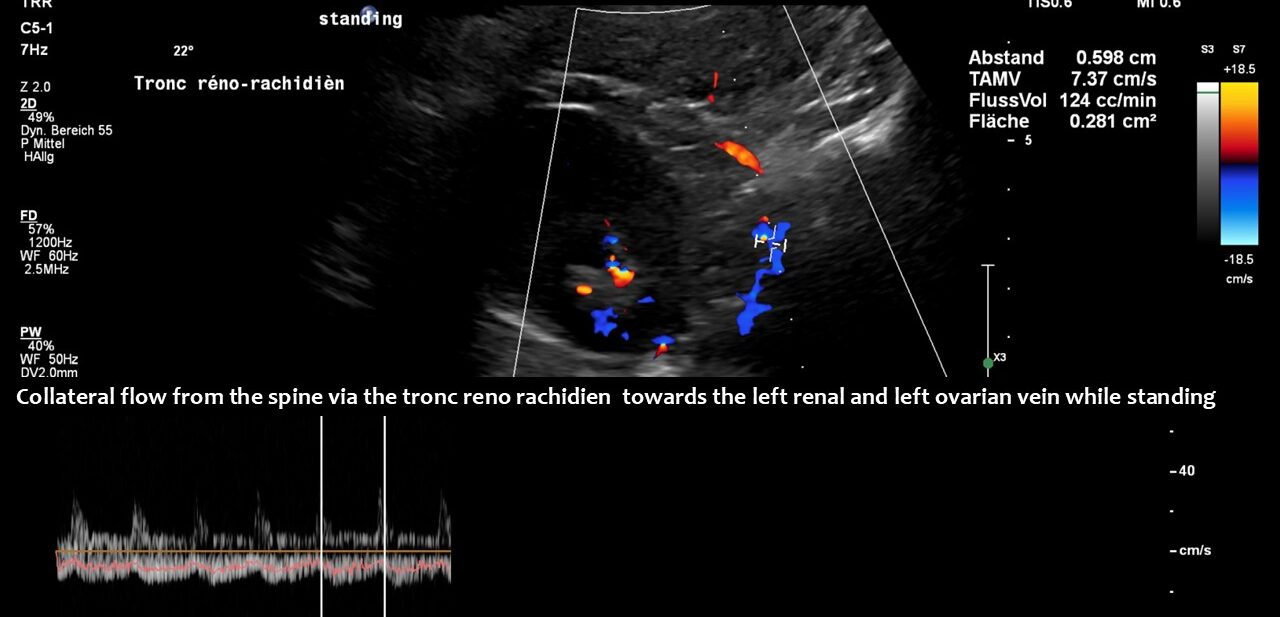

The main driving force was the compression of the left renal vein, as this vein transports most of the blood in the lower body hemisphere. Compression of this vein forces blood to run down the left ovarian vein towards the left internal and common iliac veins. The blood then tries to cross the spine to reach the inferior vena cava. This vessel returns blood to the heart. However, in this patient, the left common iliac vein was also compressed. Consequently, the increased pressure in the left renal vein could only be relieved by creating an additional collateral pathway. This connects the left renal vein with the spinal canal and is called tronc réno-rachidièn .

Large volumes of blood from the left renal vein enter the spinal canal and run along the spinal veins (epidural plexus) towards the skull, entering the intracranial sinuses. They can then leave the skull via the vertebral veins, but mainly via the jugular veins.

Only a four-dimensional volume flow measurement of the jugular veins can determine the cause of the daily headaches. The overall reduction in venous outflow from the brain in both jugular veins, totalling 258 mL/min, is significantly lower than the normal average volume of 719 mL/min. Consequently, the patient can eliminate only 36% of the required flow volume, while additional volume is forced into the skull from the left renal vein via the tronc réno-rachidien and from the left common iliac vein via the left ascending lumbar vein. This results in a chronic increase in intracranial pressure, as demonstrated by the elevated cerebrospinal fluid pressure obtained through a lumbar puncture. When the left jugular vein is also completely compressed due to increasing cervical lordosis when upright, the headaches become unbearable, accompanied by additional neurological symptoms as described by the patient.